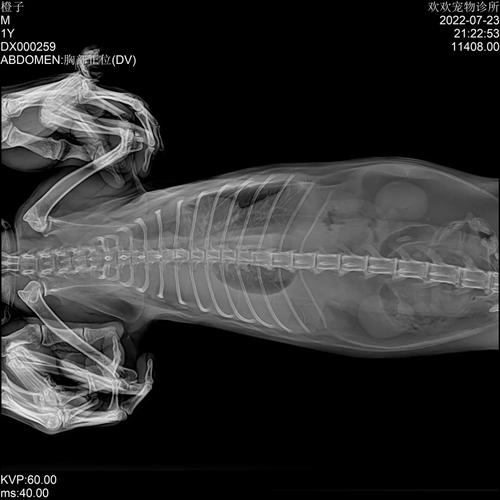

〖Three〗、猫咪胸腔积水是有救的,但是需要注意以下问题,第一:胸腔积水是由于受外伤、器官病变等导致胸腔渗透压的改变,使循环中的体液聚集在胸腔,会严重影响猫咪呼吸和心跳。第二:需要进行X光检查确诊胸腔积水的具体情况,此外再进行手术治疗,术后输液比较好添加白蛋白。